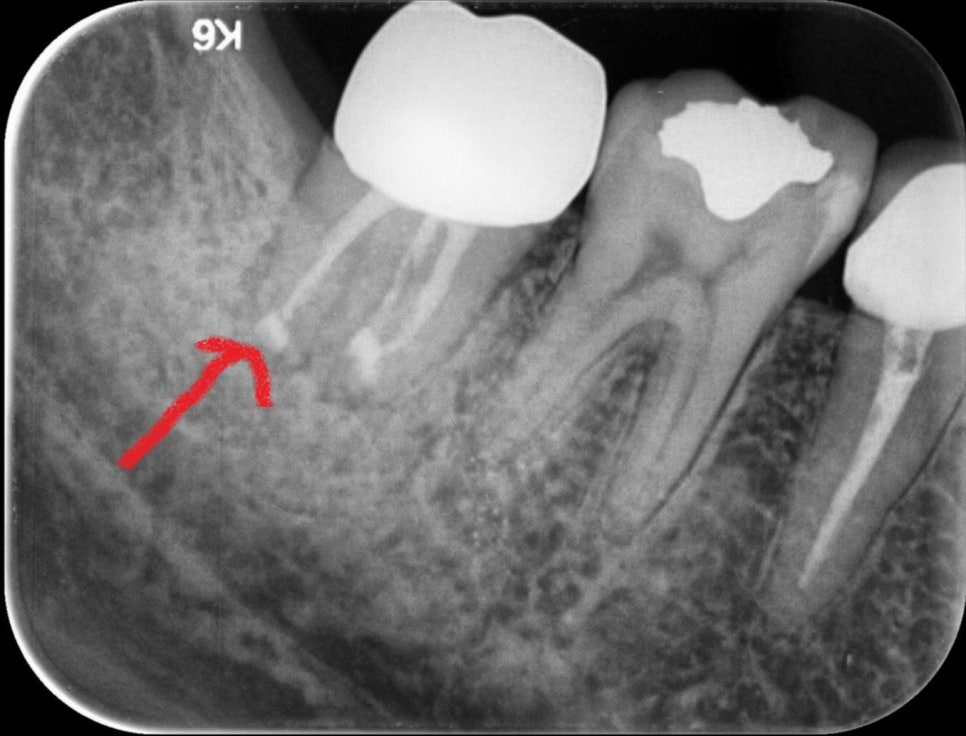

하지만, 뿌리 끝에 신경관의 분지인 부근관이 있는 경우, 치과용 바늘이 접근하기 어려워 신경이 모두 제거되지 않아 통상적 신경치료가 마무리되어도 통증이 좋아지지 않는 드문 경우가 있습니다. 이때 우리는 치아재식이라는 치료법을 시도해 볼 수 있습니다.

얼마 전 조00이라는 환자분이 신경치료를 모두 마친 후 금으로 크라운까지 세팅된 치아에 통증을 호소하시면서 내원하셨습니다. 아직 나이도 어리고, x-ray나 CT로 염증을 확인하기 어려웠습니다.

이러한 경우 발치하고 임플란트를 해야 하나요?라고 질문하시더군요. 발치하기 전 치아를 살릴 수 있는 재식술에 대해 설명 들으시고 당일 바로 진행되었습니다.